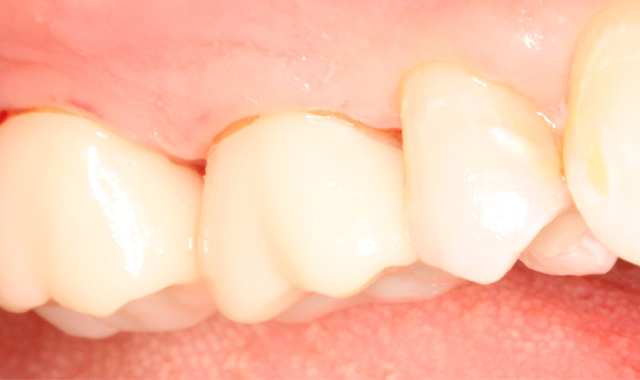

Fig. 1 Fig. 2

A 53-year-old male presented with a treatment plan to replace an existing f rst molar crown and prepare a crown on a second molar (Figs. 1-2).

The patient was anesthetized and tolerated the crown preparations well. Both zirconia-style preparations were digitally scanned and those scanned impressions were sent to an off-site lab. Temporary crowns were fabricated and worn for two days. Upon return, the temporary crowns were immediately removed. Notice the healthy condition of the gingiva (Fig. 3).